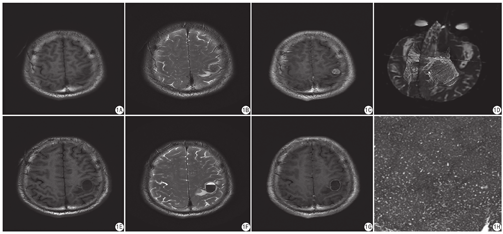

患者男,50岁。六年前左前胸壁一黑痣反复脱皮、触之易出血,遂切除。术后病理:恶性黑色素瘤。现患者因头晕、行走困难、右手麻木入我院。头颅MRI示左侧顶枕叶类圆形占位,病灶上方呈类圆形T1WI、T2WI稍低信号,大小约13 mm×12 mm,增强扫描呈结节状强化,边缘见强化环;病灶下方见T2WI高低信号液平面,范围约17 mm×22 mm×21 mm;病灶周围可见斑片状T2WI高信号影。DTI示占位处神经纤维束略受压(图1A~G)。随后在我院手术治疗。影像诊断:应排除单纯性出血,考虑转移瘤继发出血可能性大。术中所见:肿瘤呈红色鱼肉状,血供极其丰富,质地软。病理诊断:肿瘤细胞呈片状弥漫或巢状分布,细胞界不清,核异型性显著,核仁明显,核分裂多见,胞浆淡染(图1H)。免疫组化:肿瘤细胞HMB45 (+)、MelanA (+)、S-100(+)、Ki67 (35%+),符合恶性黑色素瘤。

黑色素瘤内含有大量的由顺磁性黑色素颗粒形成的金属螯合物,可以缩短T1、T2弛豫时间,因此其典型MRI表现为:T1WI高信号、T2WI低信号,增强扫描明显强化[4]。但是并不是所有黑色素瘤都具有该典型的MRI征象,需要取决于瘤内黑色素含量及出血量,本例就是一例不典型黑色素瘤。研究人员依据瘤内黑色素含量的不同将其MRI表现分为四类:(1)黑色素型:瘤内含有丰富的黑色素颗粒,MRI表现典型,为T1WI高信号,T2WI低信号;(2)无黑色素型:瘤内不含黑色素或含量低,表现为T1WI低信号,T2WI高信号;(3)混合型:无特异影像特征;(4)血肿型:表现为血肿不同时期的信号特征。其中以黑色素型、血肿型最多见,占70%[5]。因此本病例属于混合型黑色素瘤。